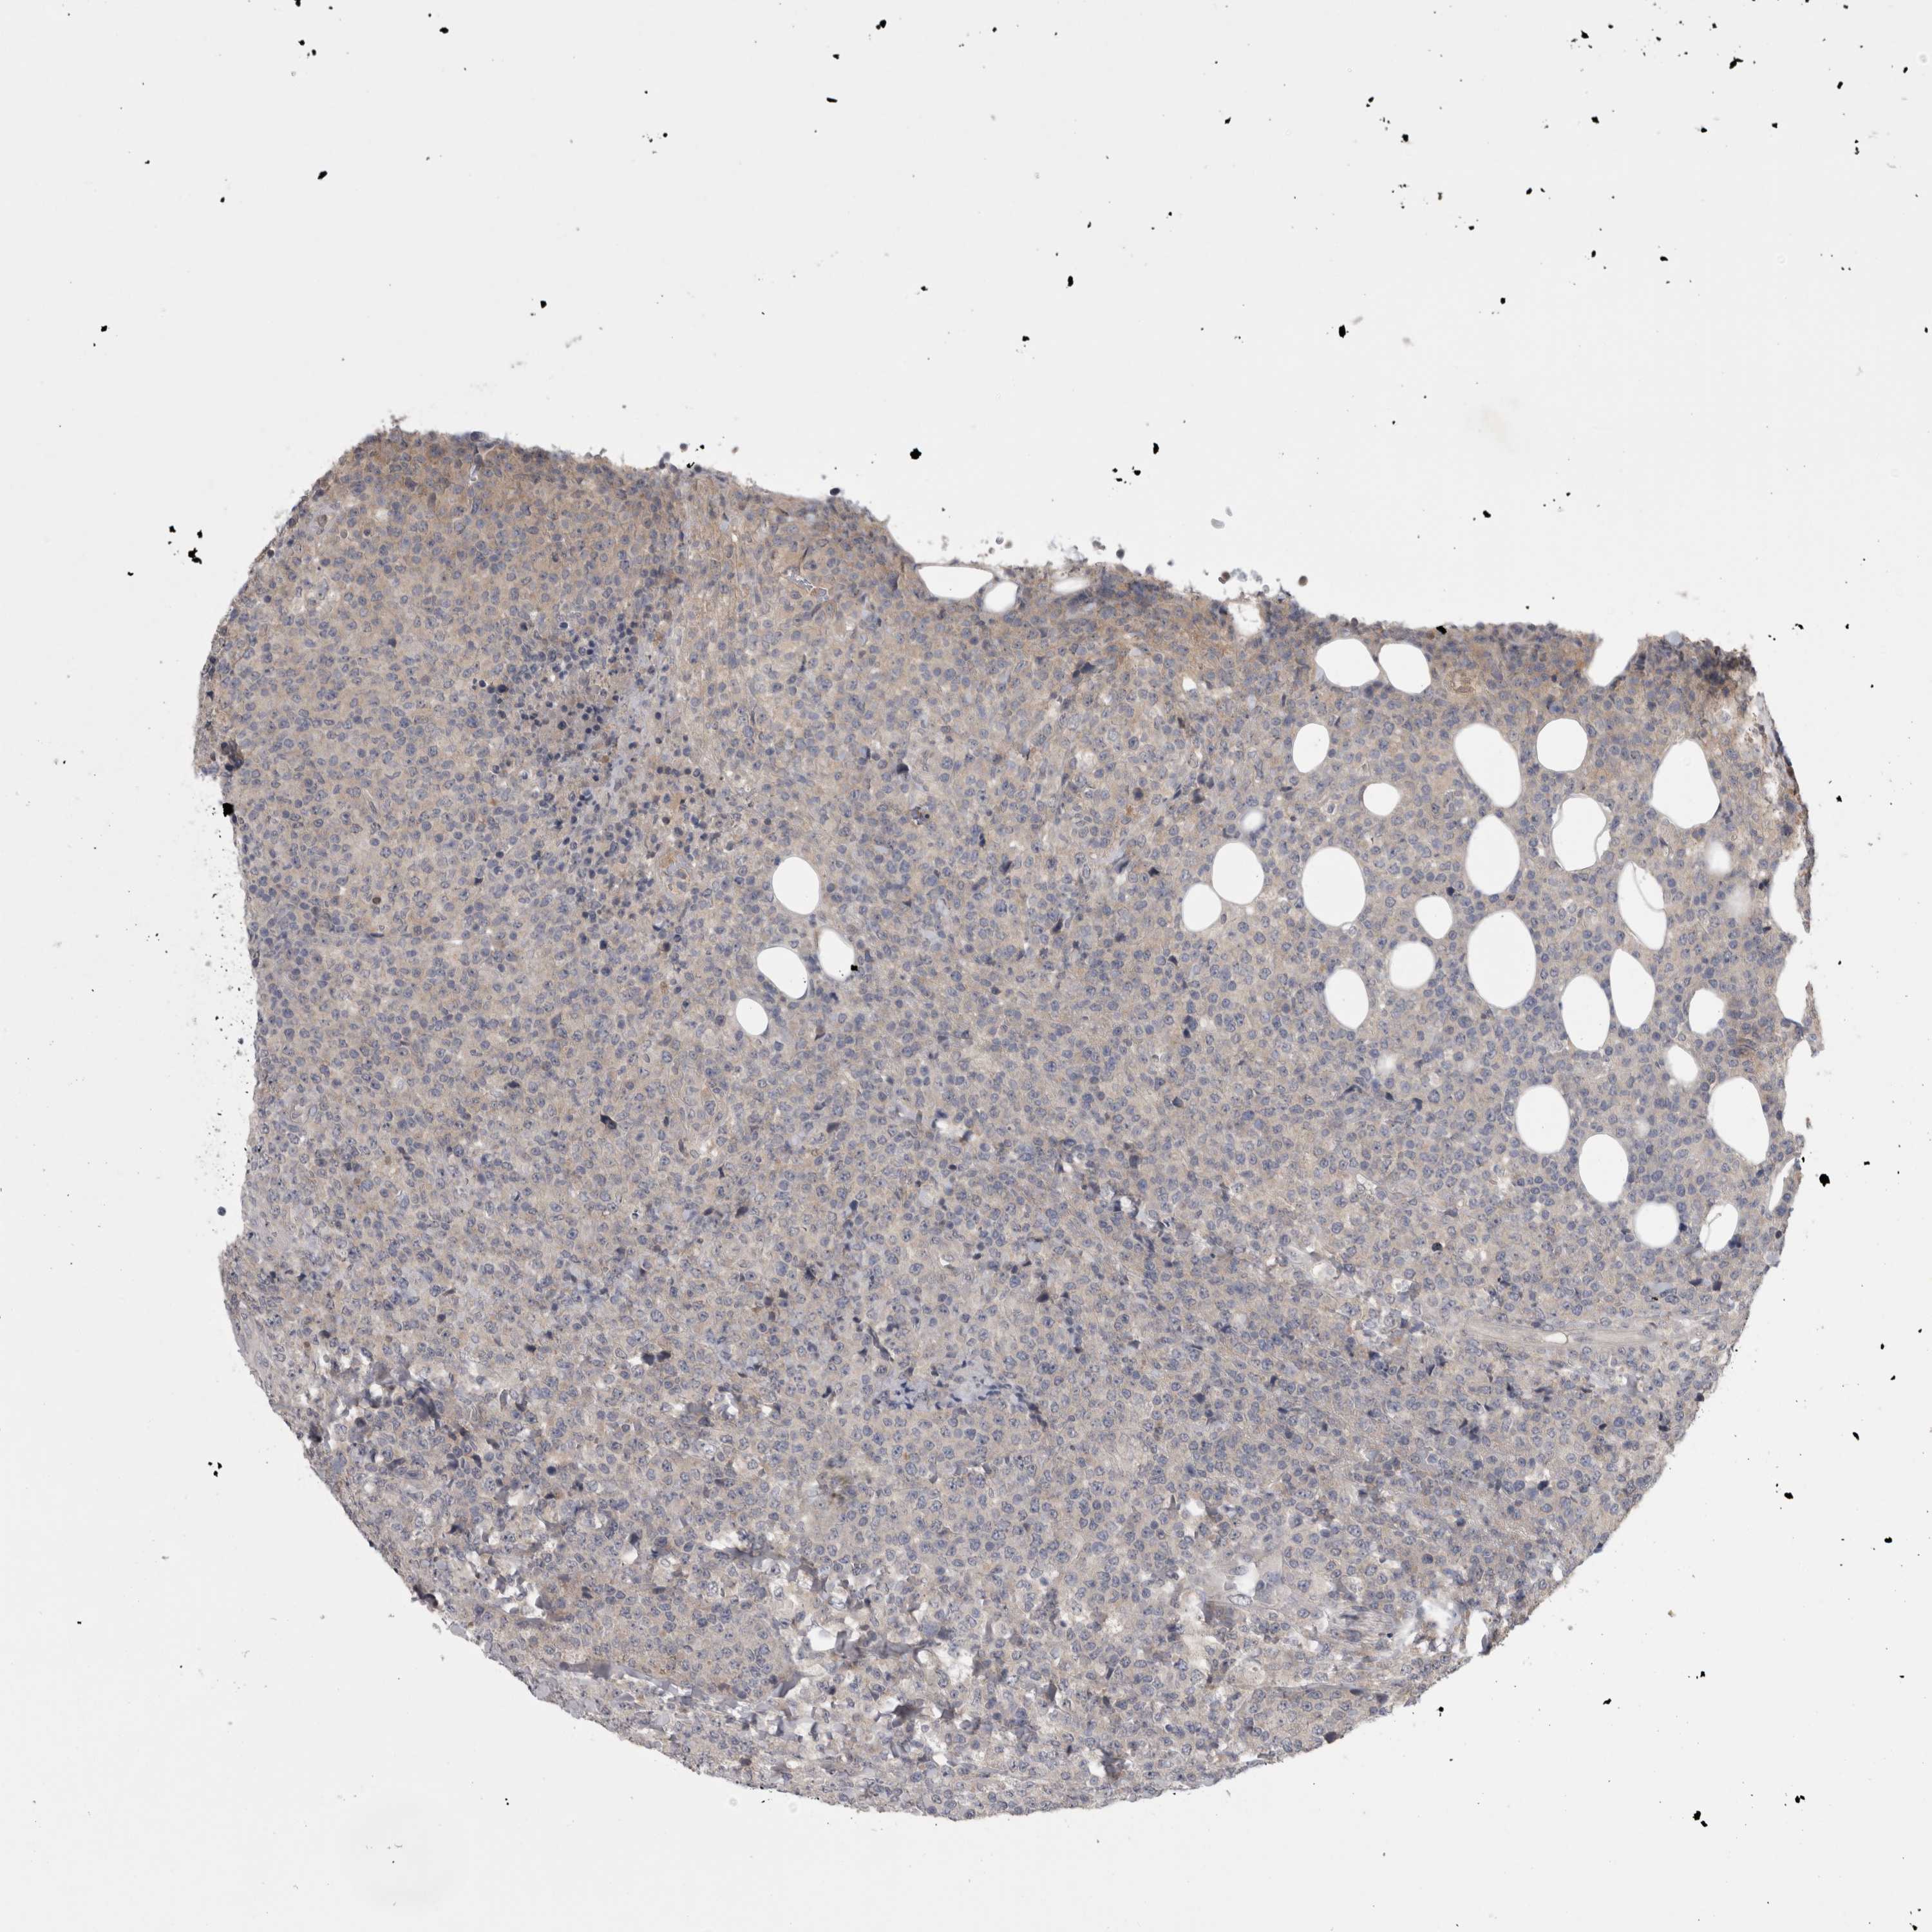

CANCER LYMPHOMA Show tissue menu

LYMPHOMA - Protein expressioni

A mouse-over function shows sample information and annotation data. Click on an image to view it in a full screen mode. Samples can be filtered based on level of antibody staining by selecting one or several of the following categories: high, medium, low and not detected. The assay and annotation is described here.

Each image is clickable and will lead to virtual microscopy that enables deeper exploration of all samples and also displays staining intensity scores, fraction scores and subcellular localization as well as patient and tissue information for each sample.

Antibody HPA025019

Hodgkin's disease, NOS

Malignant lymphoma, non-Hodgkin's type, High grade

Malignant lymphoma, non-Hodgkin's type, Low grade